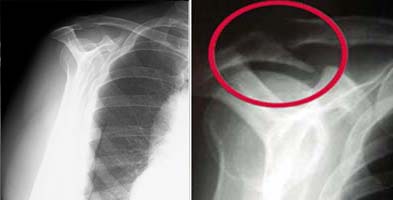

(Left) Normal outlet view x-ray. (Right) Abnormal outlet view showing a large bone spur causing impingement on the rotator cuff.

X-rays. Becauses x-rays do not show the soft tissues of your shoulder like the rotator cuff, plain x-rays of a shoulder with rotator cuff pain are usually normal or may show a small bone spur. A special x-ray view, called an "outlet view," sometimes will show a small bone spur on the front edge of the acromion.